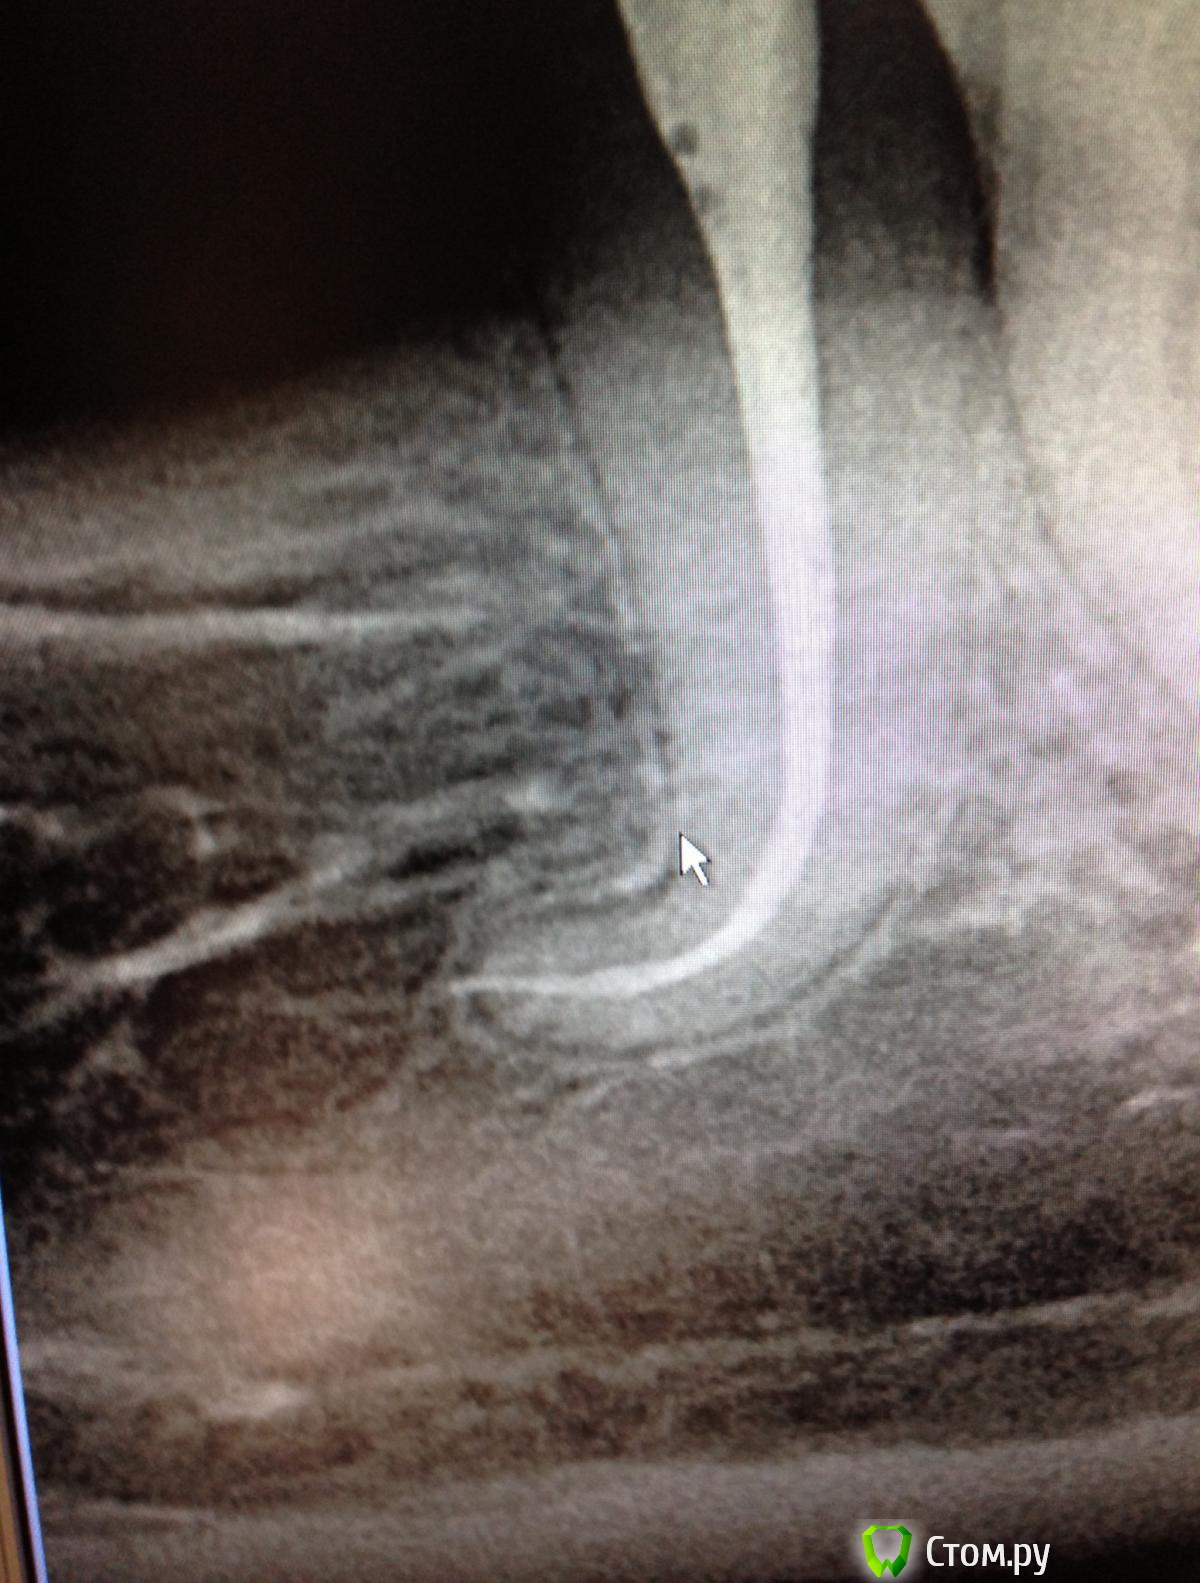

Kolchanov Опубликовано 18 августа, 2014 Поделиться Опубликовано 18 августа, 2014 А подскажите если канал допустим обработан на всю раб длинну 35/04,то какую гутту брать 02 конусности для латералки?35/02 не убежит за апекс? Ну вы же упор формируете?http://s61.radikal.ru/i174/1408/d5/267d539a4bb2.jpgПосле 35.04 я обычно дорабатываю 40.02 ручным. Ссылка на комментарий